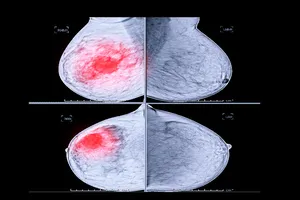

유방암은 여성에게 가장 흔한 암이며, 조기에 발견하면 치료 성공률이 높아집니다. 유방암 검사는 조기에 발견하기 위한 필수적인 검사이며, 여성의 연령, 건강 상태, 가족력 등에 따라 검사 시

유방암 초기증상, 치료, 수술 방법, 수술 비용까지

여성에겐 가장 흔한 암인 유방암은 조기에 발견하고 치료하면 완치 가능성이 높습니다. 하지만 많은 여성들이 유방암의 초기증상을 알지 못하거나 무시하여 후회하는 경우가 많습니다. 오늘은